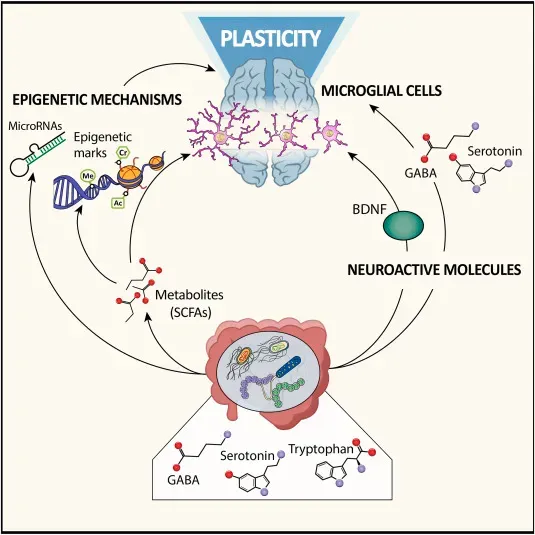

One of the most empowering findings is that brain plasticity is not driven only by rare, heroic efforts, but by ordinary daily habits. Regular physical activity improves blood flow to the brain, supports the growth of new connections, and is linked with better memory in older adults. A pattern of sleep that allows for deep, uninterrupted cycles helps the brain consolidate new information and clear out metabolic waste. Diets that emphasize whole foods, fruits, vegetables, and healthy fats appear to support long‑term brain health more reliably than highly processed alternatives.

Cognitive challenges matter as well, but they do not need to be exotic. Joining a book club that reads demanding material, learning a new card game with friends, or finally tackling that foreign language app you have been ignoring can all nudge the brain into forming new pathways. Social interaction adds another layer, as conversations require rapid processing, memory, and emotional attunement. Think of these habits as the daily “training environment” in which your brain decides whether to maintain and upgrade its circuits or slowly let them go unused.